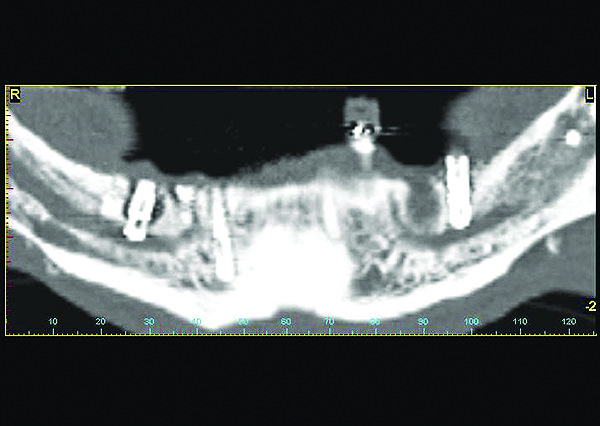

Two implants which damaged the inferior alveolar nerve causing irreversible bilateral numbness in the lip, soft tissues, and teeth innervated by this branch of the mandibular nerve. This is considered a major complication.

Figure 7